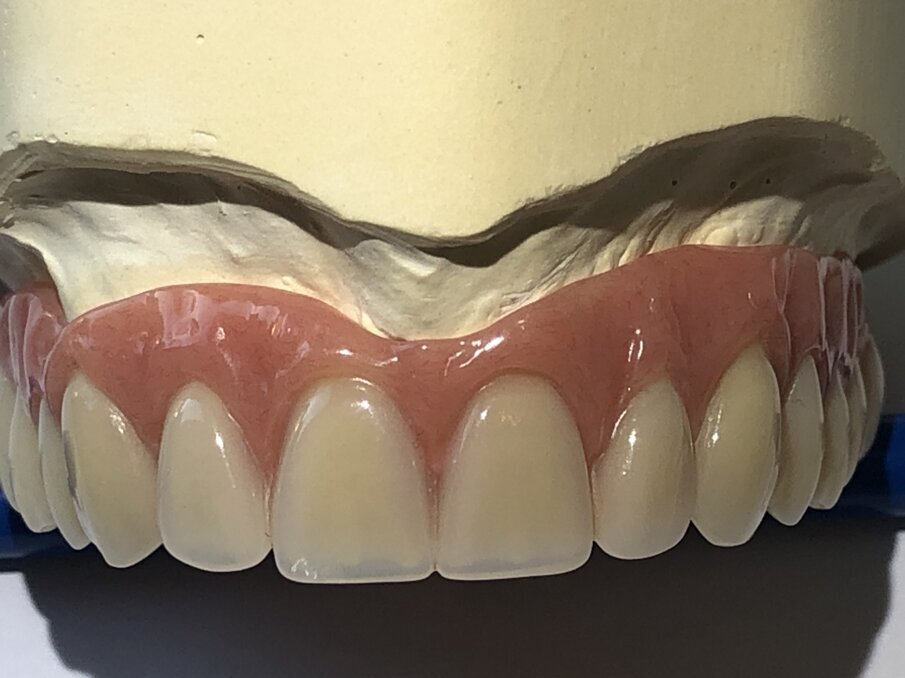

Dankzij onze nieuwe werkwijze worden de protheseranden sierlijker, welgevormder en vanzelfsprekend in de bovenkaak gehemeltevrij. In tegenstelling tot de standaardconstructie waarbij drukpunten ontstaan door minimale bewegingen, is dat in deze nieuwe constructie niet het geval. Het kunststofgedeelte in het secundaire gedeelte van de prothese kan indien nodig zonder veel moeite worden vervangen.